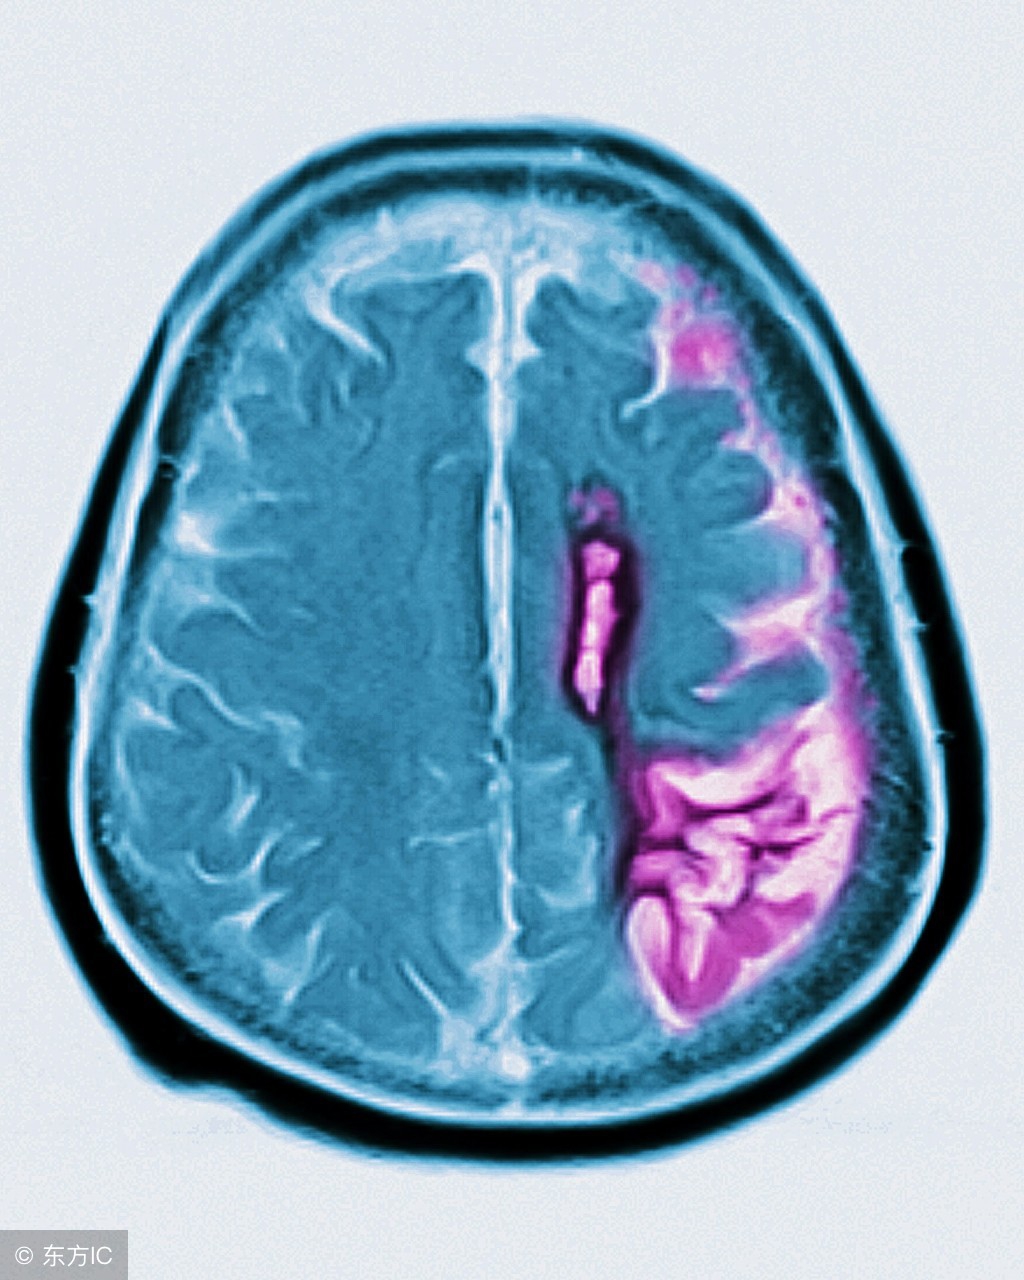

脑萎缩是一种家族显性遗传神经系统疾病,只要亲代其中一人为此疾病患者,其子女将有50%的机率遗传此症并发病。脑萎缩患者的关注事项有哪些你知道吗?